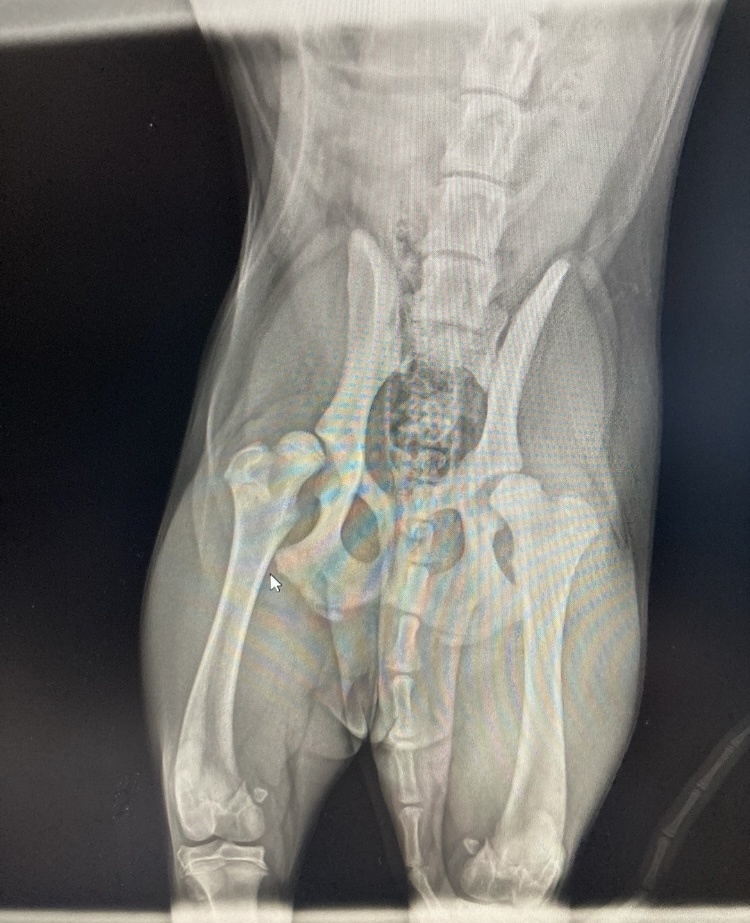

это самый первый снимок, как искали травму, но по нему сразу видно, что бедренные косточки не плотно сидят.

1) сделали КТ, что б определить масштаб проблемы (у нас угол отклонения от нормы составлял 28%, где в щенячестве до 15% можно обойтись наблюдением и контролем состояния до полного формирования костных структур). так мы поняли, что нужно уже вмешиваться в протекающий процесс развития заболевания.